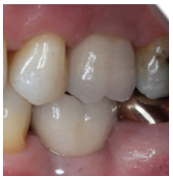

Following periodontal re-evaluation confirming gingival health and adequate patient compliance, the extraction of 16 with alveolar ridge preservation was scheduled. The roots of the 16 were sectioned and removed. The socket was preserved using a xenograft. Careful elevation of the facial and palatal mucosa was performed in order to create a pouch that would stabilise a collagen membrane. After 20 weeks of healing, the gingiva was of mature aspect with no signs of infection. The patient returned for planned surgical placement of a suitable 4.6 × 10.5mm BioHorizons Tapered Internal dental implant with a Laser-Lok collar, and the assistance of a fabricated restorative-driven surgical template for surgical placing. In view of the adequate amount of keratinised mucosa and excellent primary stability, a non-submerged surgical approach was selected (Figure 1 and 2).

From Left to right; 1. Radiograph of placed implant with healing abutment. 2. Photograph of healed gingiva 10-weeks post-op. 3. Radiograph 1-year post-op. 4. Photograph 1-year post op of restored implant.

Patient presented 10-weeks after the implant placement, proper osseointegration was confirmed and the fixture was restored by a specialist Prosthodontist. At the 1-year supportive periodontal appointment, a diagnosis of healthy peri-implant tissues was confirmed (Figure 3 and 4).